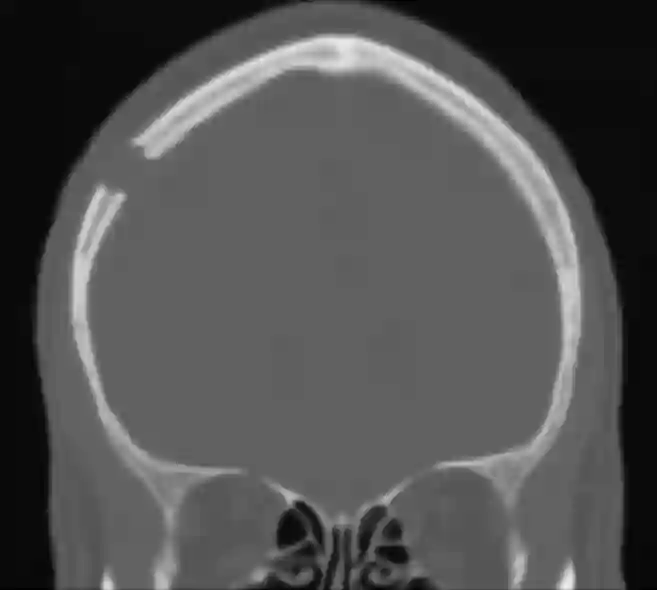

Bohrlochtrepanation CT

Abbildung einer coronaren CT Bildgebung im Knochenfenster bei einem Patienten nach durchgeführter rechtsseitiger Bohrlochtrepanation.